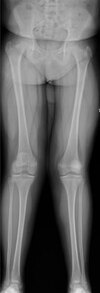

Describe the normal physiologic knee aligment in kids? *Physiologic bowing of the lower extremities should spontaneously correct by what age?* graft is shown

Tibia vara is considered physiologic in children younger than 2 years. Physiologic tibia vara should resolve between ages 2 and 3 years. If tibia vara is present or worsening by age 3 years, a diagnosis of Blount disease should be considered. AAOS *It usually resolves by 2 years of age but there is great variability. By age 36 months, almost all children will correct spontaneously.* ## Footnote In children with physiologic bowing, the screening examination is typically normal and a family history is absent; therefore, radiographs are not necessary. If the deformity has not resolved by age 2 years, an AP radiograph of the lower limbs should be obtained. This provides documentation of the severity of the bowing, permits measurement of the metaphyseal-diaphyseal angle and/or Langenskiold grade, and allows evaluation for conditions such as rickets or bony dysplasia. No treatment is indicated for physiologic bowing.